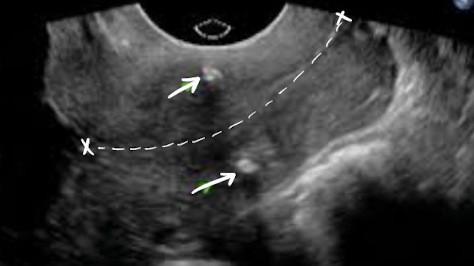

SONO: cervical cerclage

post-cerclage procedure; imaged transvaginally

cerclage stitches are echogenic with posterior shadowing

serial scans may be done to ensure cerclage remains secure and cervix is closed

what are the arrows pointing to?

cervical cerclage stitches